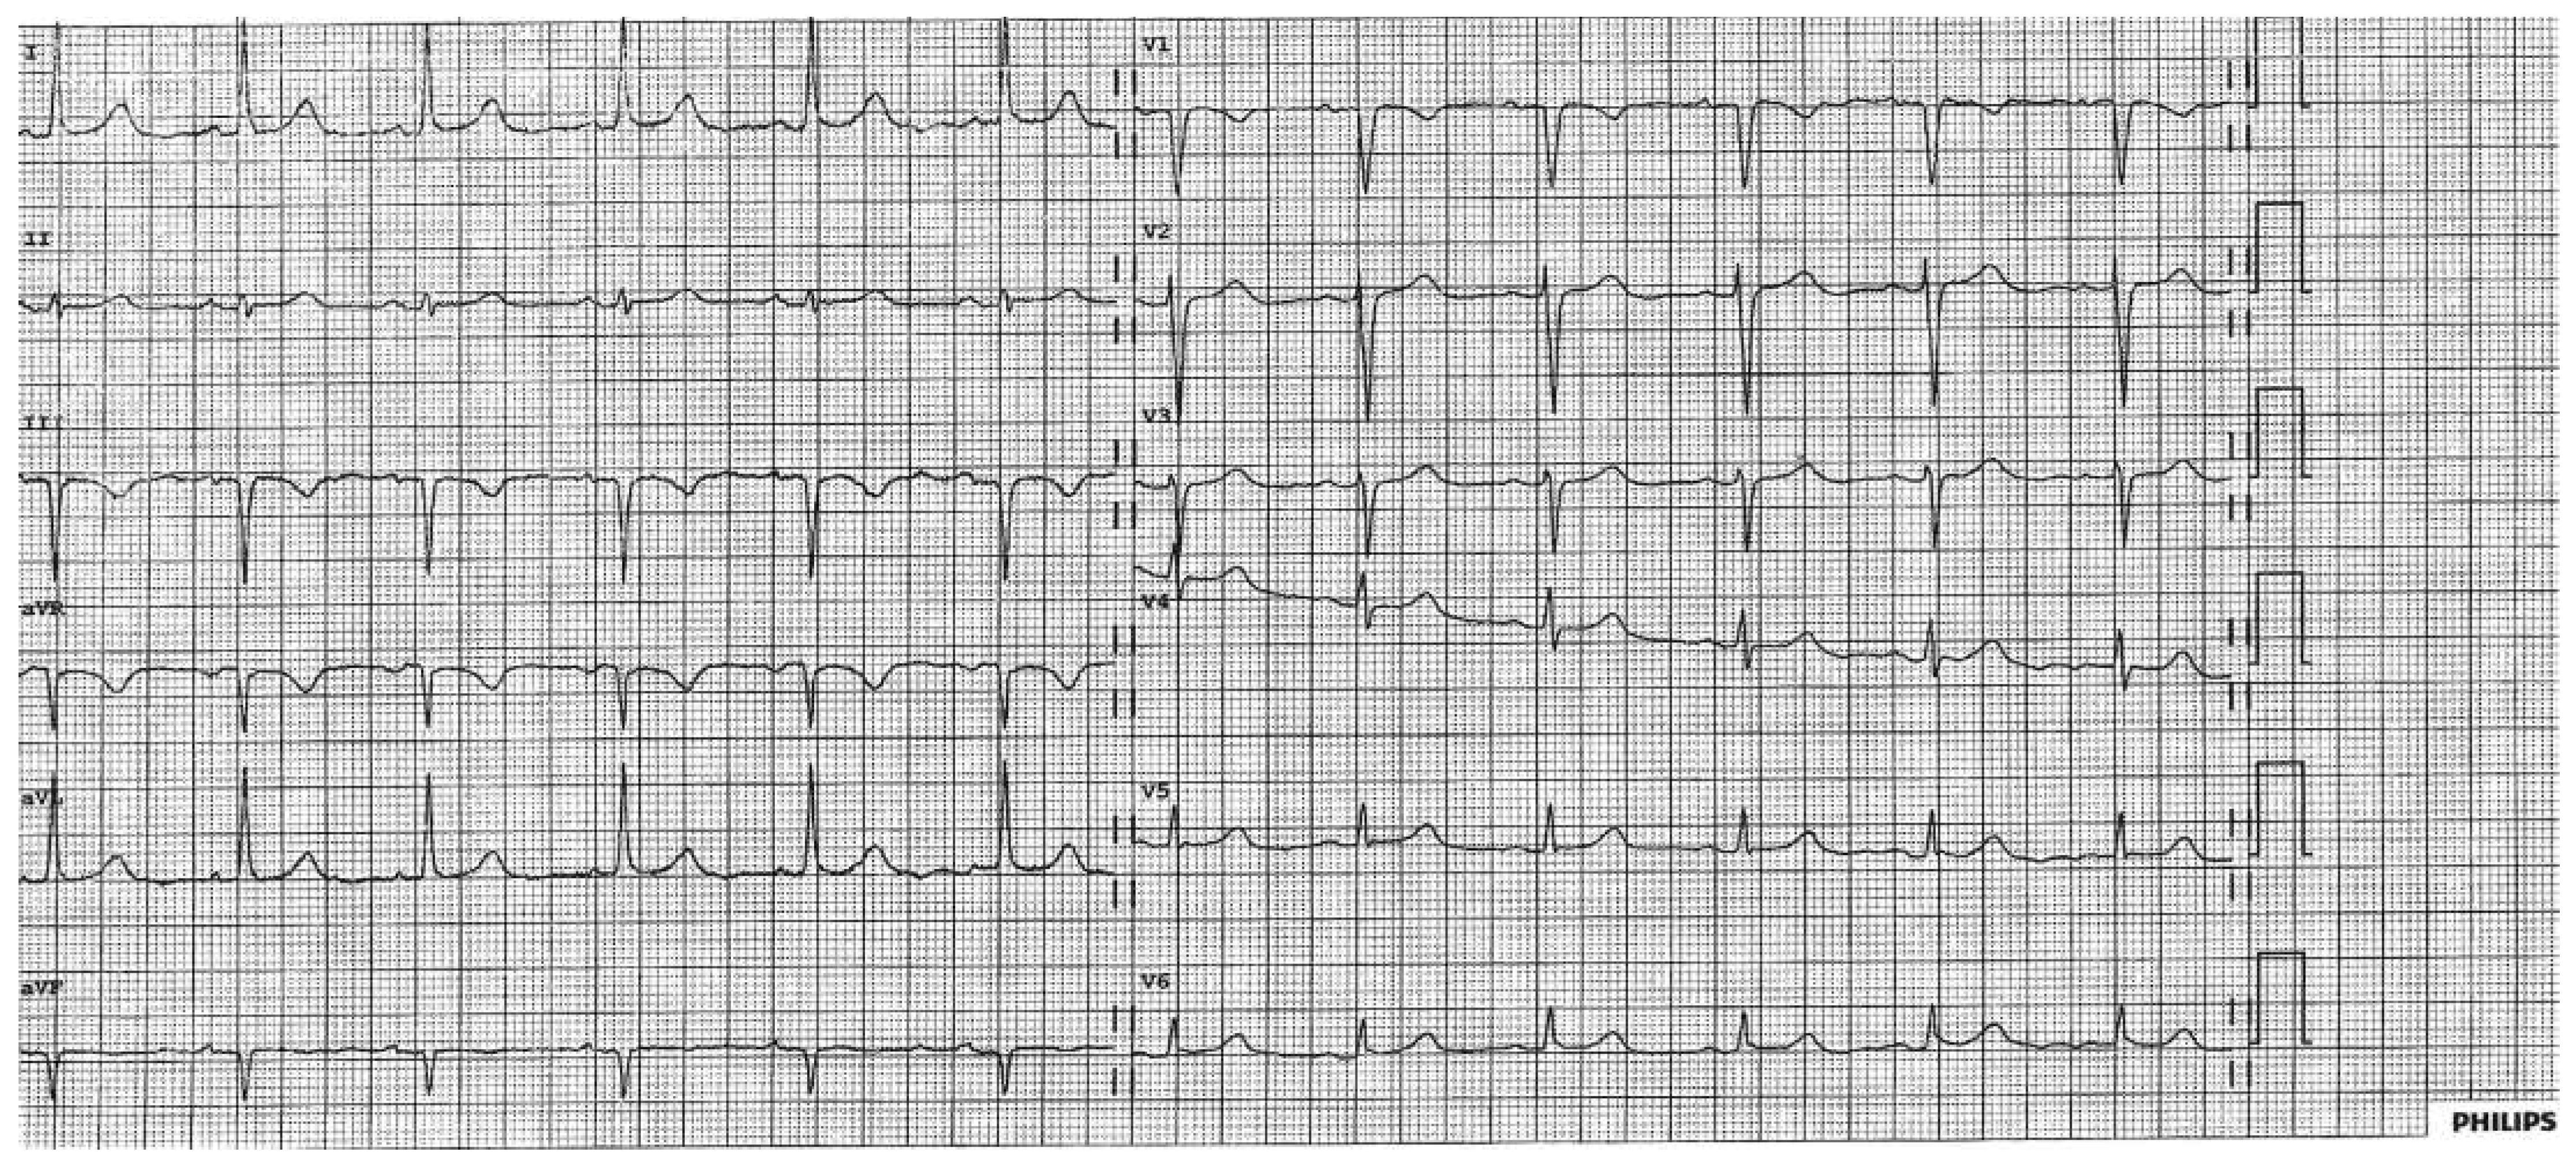

A 68-year-old, obese (body mass index 27 kg/m2) woman without prior cardiac history was admitted for an elective laparoscopic cholecystectomy. One hour after she was transferred to the intermediate care unit, she complained of chest pain and had a systolic blood pressure of >200 mm Hg. Physical examination was normal and the ECG (Figure 1) demonstrated low voltage in the precordial leads but normal voltage in the peripheral leads.

Figure 1. A: Low voltage in the precordial leads with ECG electrodes positioned in the ordinary manner.